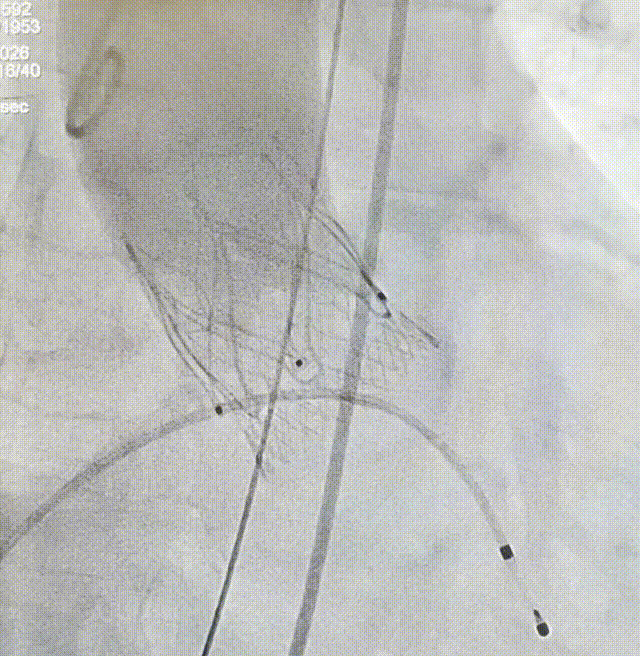

2026年伊始,TaurusTrio经导管主动脉瓣系统在复旦大学附属中山医院,浙江大学医学院附属第二医院,中国医学科学院阜外医院,首都医科大学附属北京安贞医院,四川大学华西医院等多家临床中心成功开展上市后全国首批植入。这不仅是TaurusTrio正式走向广泛临床应用的重要里程碑,更标志着中国单纯主动脉瓣反流介入治疗正式迈入了“心键合璧”的全新纪元。